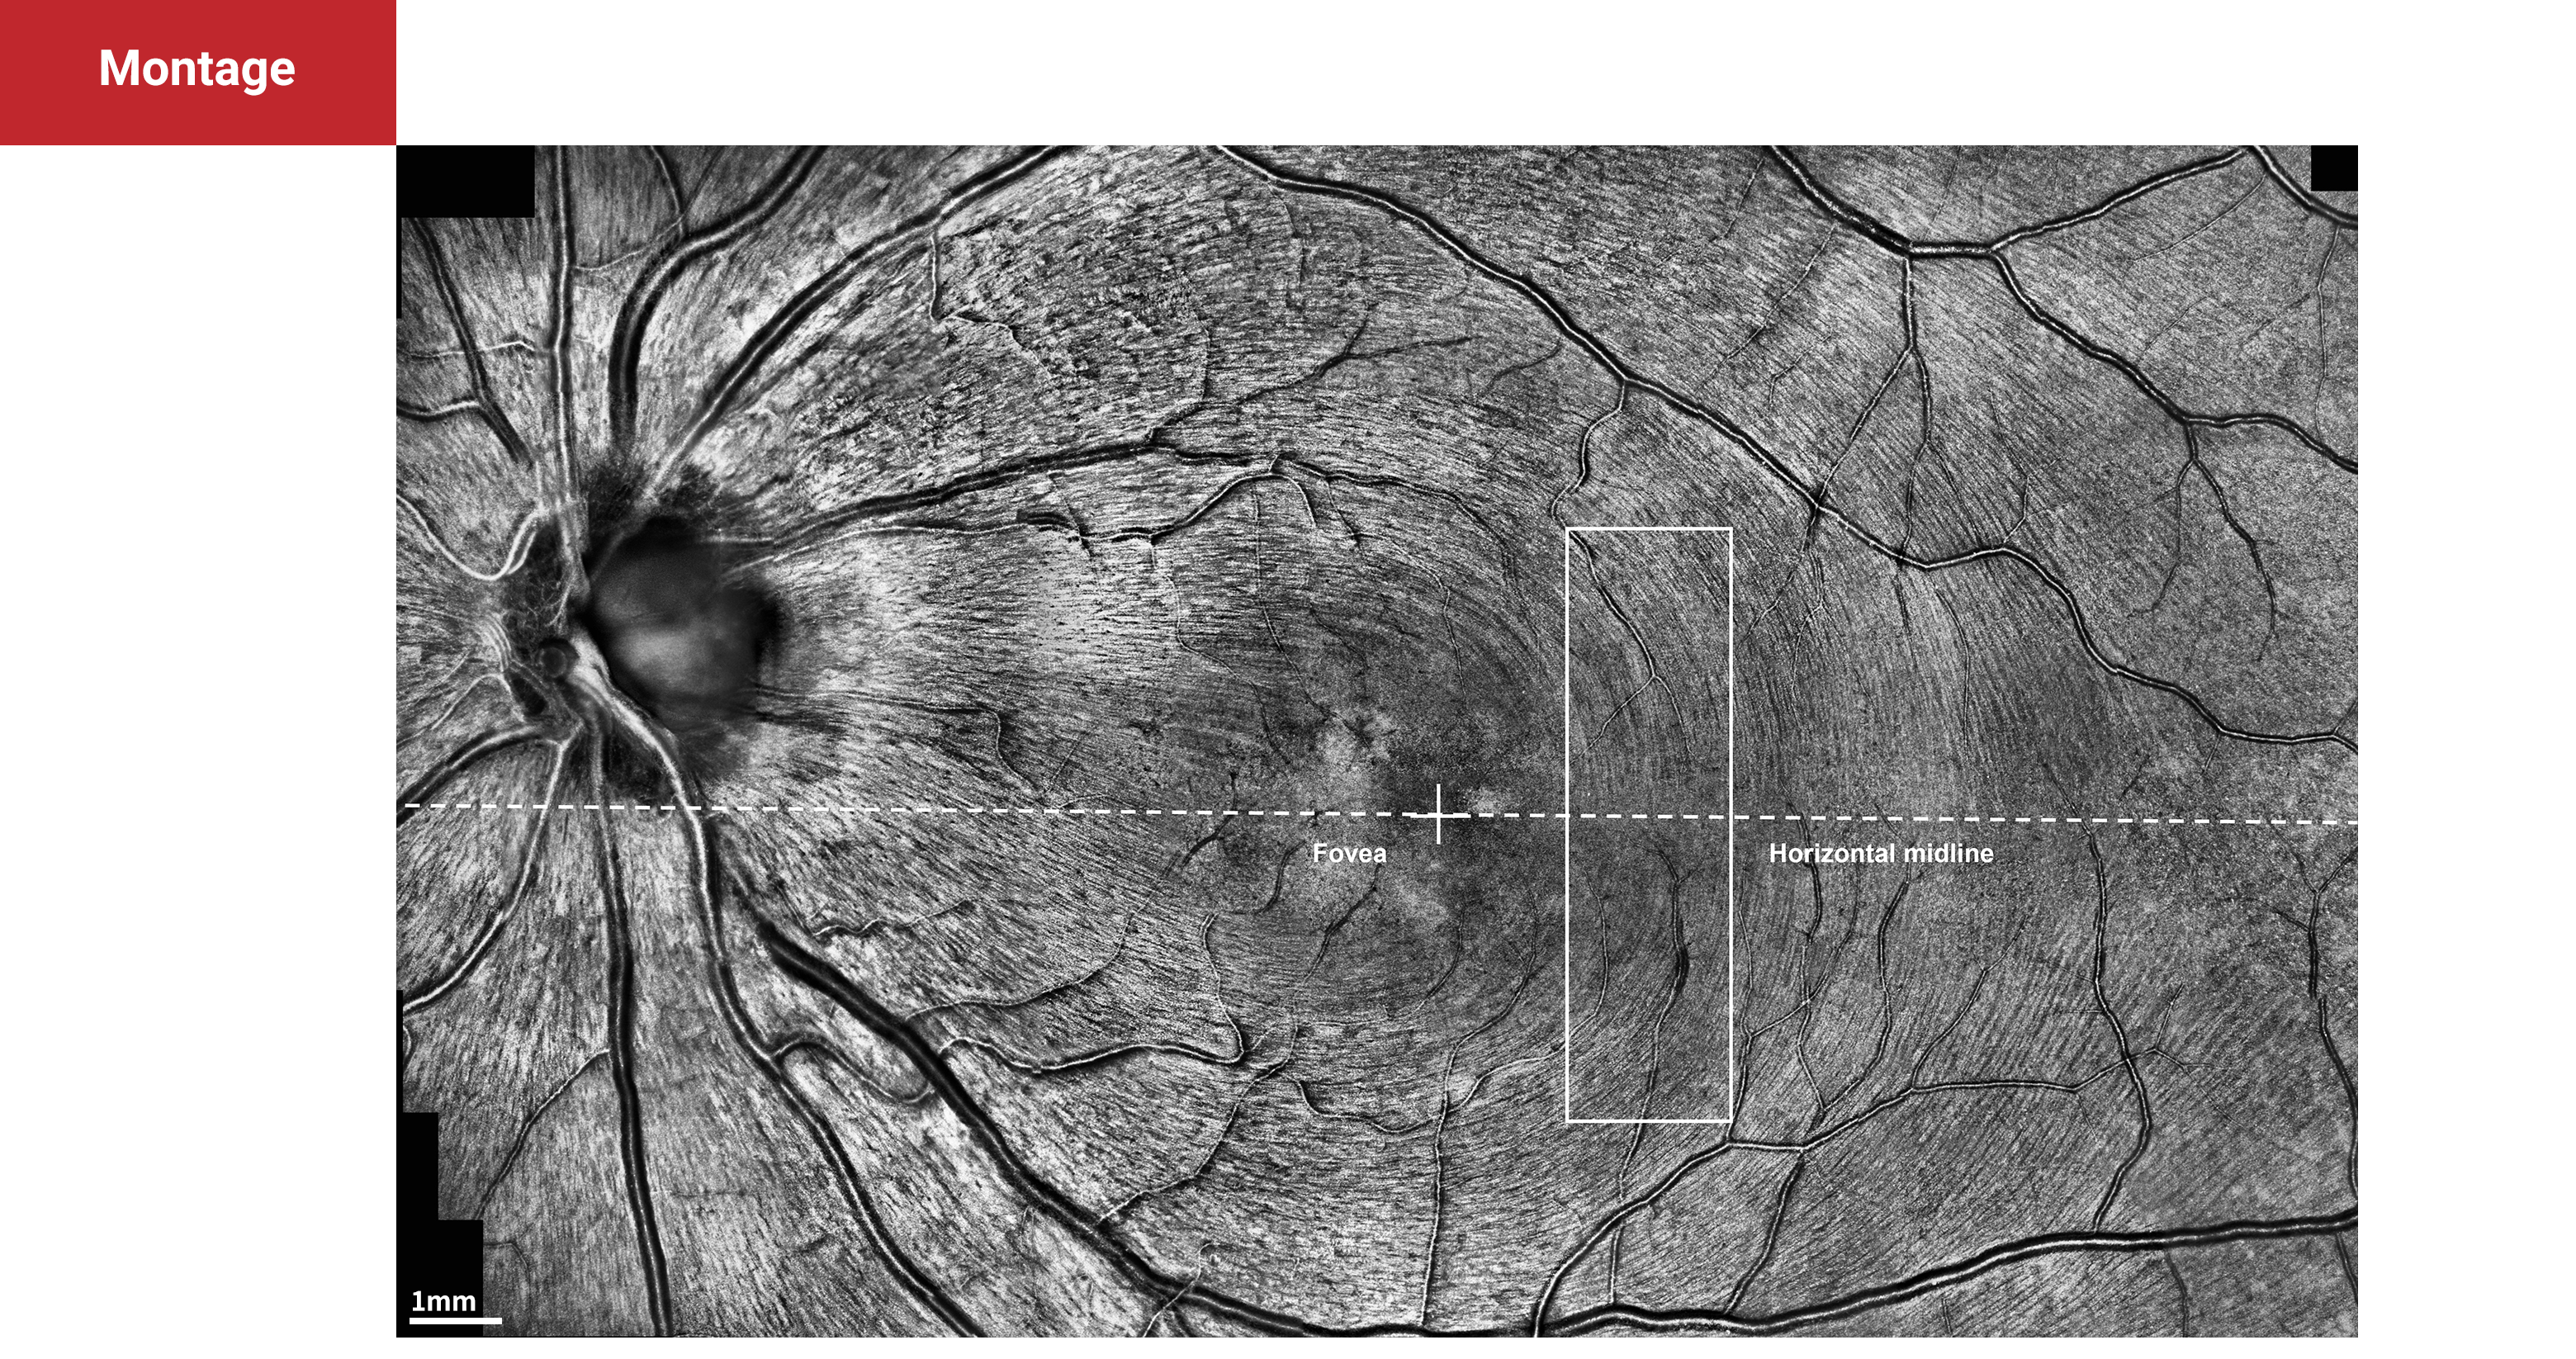

Montage